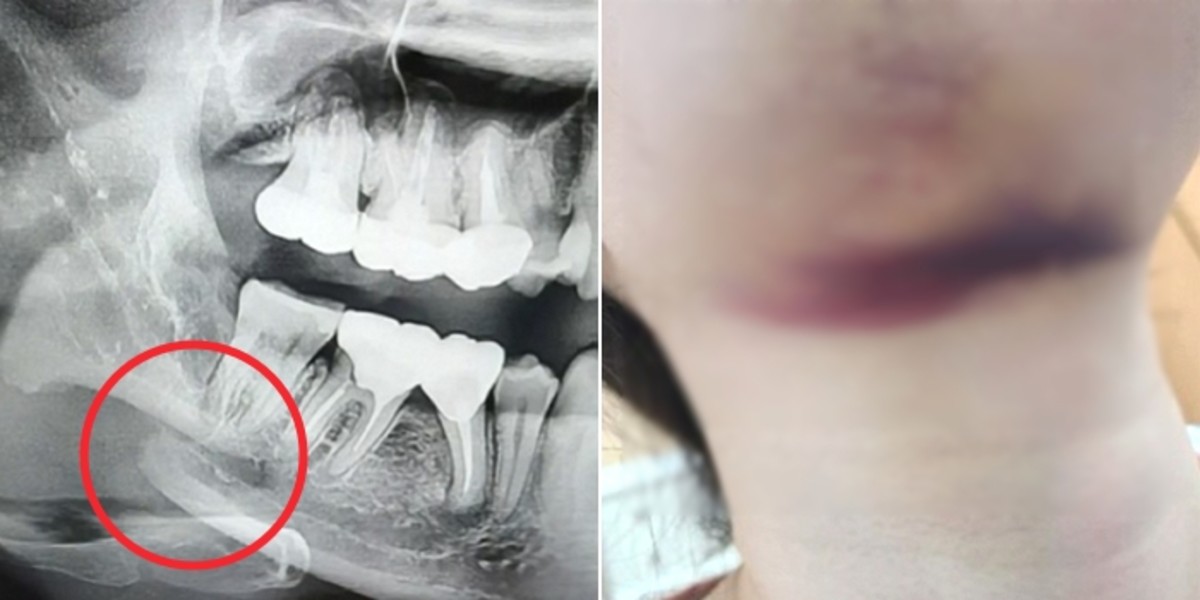

충격적이게도 A씨의 오른쪽 아래턱뼈가 부러져있었다. 그러나 의료사고를 낸 치과 측은 이를 확인한 후에도 별다른 조치를 취하지 않았다.

A씨는 결국 아픈 몸을 이끌고 홀로 인근 대학병원 응급실에 가서 수술을 받았다.

골절된 뼈에 철심을 박아 고정해야 하는 심각한 상태였다. 게다가 영구적인 치아 신경 손상까지 일으킬 수 있었다.